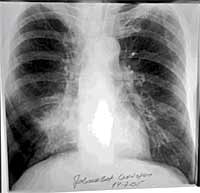

Slika 1.

Auskultatorno na plućima desno bazalno inspirijumski pukoti. Klinički nalaz na ostalim organskim sistemima uredan. Laboratorijske analize: SE 50/, Hb 109, Le 16,0. Vrednosti osnovnih biohemijskih analiza (glikemia, urea, kreatinin, AST, ALT, LDH, bilirubin) kao i nalaz u urinu u granicama referentnih vrednosti. RTG pluća i srca: bronhopneumonična senka desno parakardijalno (Slika broj 1.). Bakteriološkim pregledom sputuma nisu izolovane patogene bakterije. Citološkim pregledom sputuma nisu viđene maligne ćelije. Direknom baciloskopijom iz sputuma nisu viđeni ARB, a Löw kulture su negativne. Spirogram: restrikcijske smetnje ventilacije lakšeg stepena. EHO gornjeg abdomena: nalaz uredan. Perfuziona scintigrafija pluća sa 99 mTc - MAA: perfuzioni defekt cele donje polovine desnog pluća (Slika broj 2.).